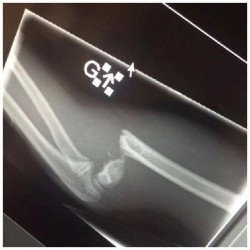

Fracture complète de l’humérus (radiographie en latéral du coude).

Fracture comminutive du tibia-péroné (radiographie de la cheville en latéral).